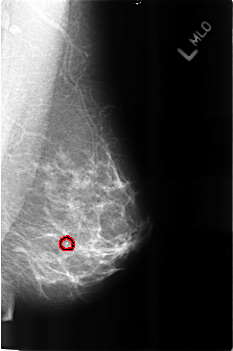

B_3160_1.LEFT_MLO

FILE: B_3160_1.RIGHT_MLO.OVERLAY

TOTAL_ABNORMALITIES 1

ABNORMALITY 1

LESION_TYPE MASS SHAPE OVAL MARGINS N/A

ASSESSMENT 2

SUBTLETY 3

PATHOLOGY BENIGN_WITHOUT_CALLBACK

TOTAL_OUTLINES 1

BOUNDARY